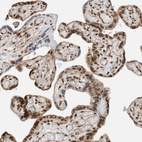

Immunohistochemical staining of human testis shows strong nuclear positivity in spermatogonia.